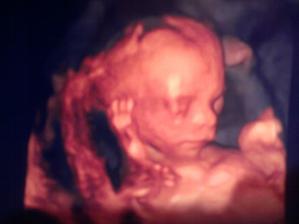

Takze je to dievcatko 🙂 a takto rastieme

17-tyzden a 3 dni...na prvom vysetreni 3D sona a skriningu,ked som cakala sok a poskodene babatko,tak akoby zazrakom je dietatko v poriadku,lekar ju podrobne poprezeral,pomeral,akurat ma drobne cisticky v hlavke a mensiu stehennu kosticku,ale o 4 tyzdne sa uvidi ako rastie a uz budu aj vsetky vysledky z genetiky..priroda je fakt silna..na to,ze som otehotnela neplodna a pod dlhodobym vplyvom Roaccutanu,som este velmi zvedava na tie geneticke vysledky..